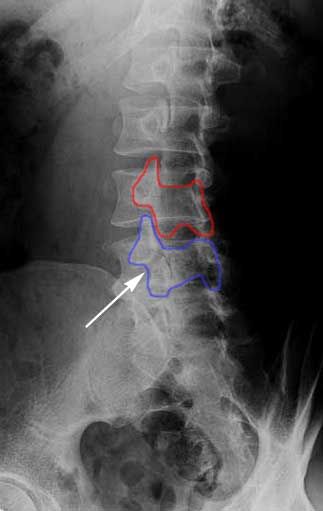

X-RAY SHOWING A PARS FRACTURE DEFECT

THE WHITE OUTLINE SHOWS THE SLIPPAGE.

Spondylolisthesis is most commonly found in the lumbar spine as these levels bear the most weight. To assess instability, we take x-rays of a patient bending forward (flexion) and bending backwards (extension). Normally there would be no motion. The more motion seen between flexion and extension x-rays across an injured level, the greater the patient’s symptoms usually appear.